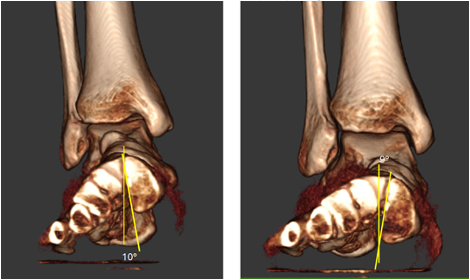

In terms of joint rotation, the first TMT joint moves in the direction of supination, not pronation in patient with HAV. Three studies using standard CT imaging compared joint positions of the medial column of the feet in both an unloaded and loaded condition. The studies compared these joint rotations in patients with HAV deformity and healthy control patients. Geng and colleagues observed that the first metatarsal moved in the direction of inversion, dorsiflexion and adduction relative to the medial cuneiform and the magnitude of this motion was greater in all 3 planes in the patients with HAV deformity.29 Watanabe found that both HAV patients and controls demonstrated equal magnitude of 5 degrees eversion of the navicular with loading of the foot, while the HAV patients demonstrated greater inversion (2 degrees) of the first metatarsal relative to the medial cuneiform than controls.45 There was minimal coronal plane rotation of the cuneiform in both groups. Kimura and colleagues found that the talonavicular joint rotated in the direction of eversion, with greater magnitude and variability in the HV group.46 At the first naviculocuneiform joint, the HAV patients showed eversion at a magnitude of only 0.2 degrees while control patients showed mild 1.5 degrees inversion. At the first TMT joint 4.9 degrees inversion occurred in the first metatarsal with loading of the foot. In addition, dorsal hypermobility of the first ray was present in patients with HAV deformity who exhibited more dorsiflexion at the first TMT joint than healthy controls. The overall net frontal plane motion of the medial column was in the direction of eversion, primarily due to motion of the navicular on the talus. Pronation motion of the navicular measured 9.6 degrees, which offset 4.9 degrees of supination motion of the first metatarsal at the first TMT joint. Therefore, when the entire foot pronates, the net pronation or eversion of the joints proximal to the first TMT articulation can ultimately place the first metatarsal everted to the ground (Figures 2A-E).

It is clear that the center of pronation rotation of the medial column of the foot in HAV patients is the talonavicular joint, not the first TMT joint. In the 3 studies of joint motion in HAV patients, the first TMT always moved in the direction of supination with loading of the foot.29,45,46